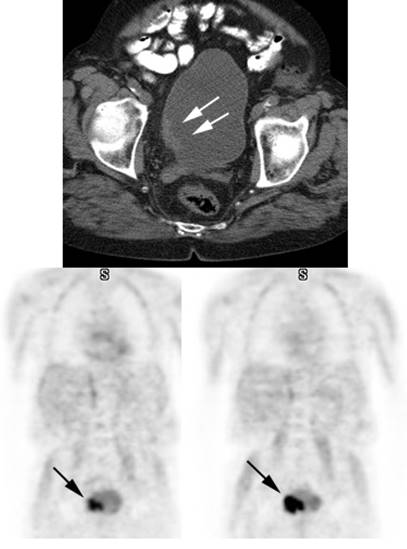

Figure 24 - Normal

uterine activity: Faint

uterine uptake is common (black arrows).

Figure 25 - Normal

testicular activity: Mild

symmetric testicular uptake can be seen (black arrows)